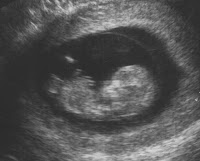

Às vezes, não há sinais de alerta eo aborto é descoberta durante uma rotina de consulta pré-natal ou um ultra-som A notícia veio como um grande choque. Pode ser difícil de entender ou aceitar, porque você não tinha idéia do que estava acontecendo dentro do seu corpo.